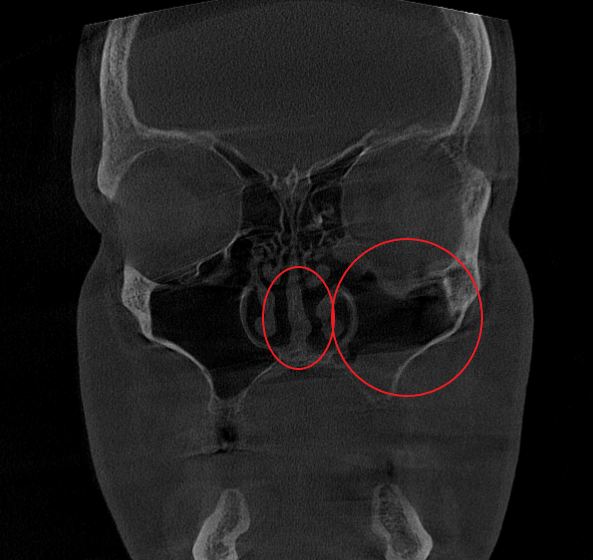

- Компьютерная томография (КЛКТ) околоносовых пазух и височных костей: Этот высокоинформативный метод диагностики объективно показал искривление носовой перегородки вправо, субтотальное снижение пневматизации (воздушности) левой верхнечелюстной пазухи, что свидетельствовало о хроническом воспалительном процессе. Костно-деструктивных изменений не выявлено.

- Хронический левосторонний верхнечелюстной синусит (J32.0). Длительное воспаление слизистой оболочки левой гайморовой пазухи, подтвержденное КТ.

Послеоперационный период протекал гладко. Проводились регулярные туалеты полости носа, промывание оперированной пазухи, назначались средства для увлажнения и регенерации слизистой оболочки, а также местная антибактериальная терапия. По результатам оперативного лечения носовое дыхание было полностью восстановлено, признаки активного воспаления купированы. Спустя 1.5 месяца после проведенного оперативного лечения проведено КТ околоносовых пазух в динамике, что отражает промежуточный результат оперативного лечения. На снимках: Перегородка носа располагается по центру, оперативно созданное соустье левой верхнечелюстной пазухи функционирует, пневматизация левой верхнечелюстной пазухи значительно улучшилась. Окончательный результат можно будет оценить через 3 месяца после проведенной операции, и при полной пневматизации левой верхнечелюстной пазухи пациент сможет приступить к установке зубных имплантов в верхнюю челюсть слева.